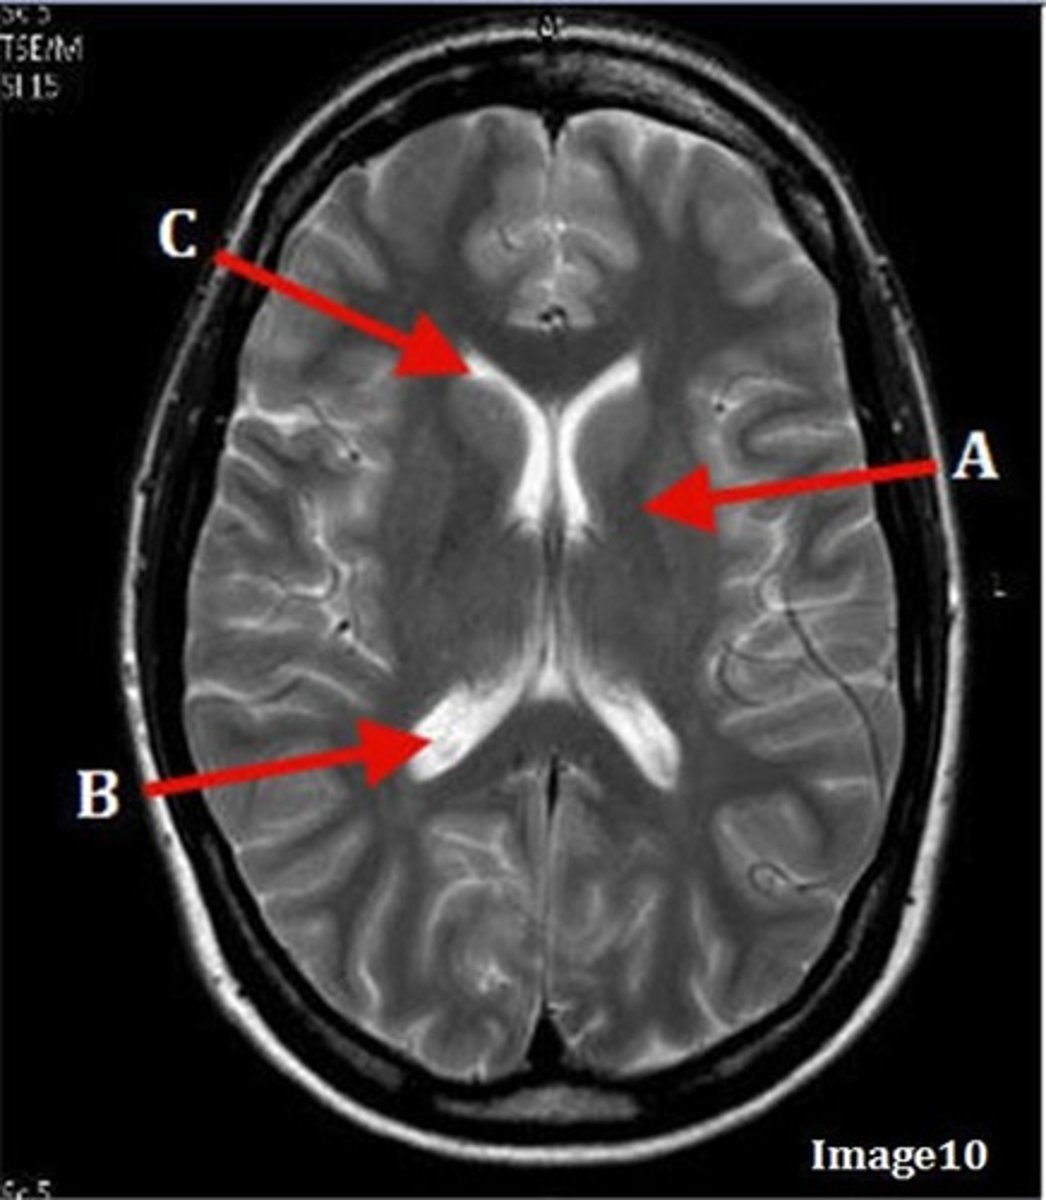

B

thalamus

A

C